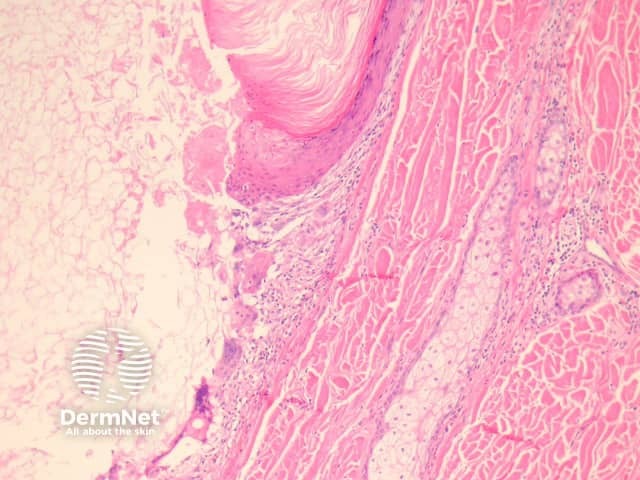

Sections of an epidermoid cyst show a cystic structure occupying at least the upper dermis but larger lesions may grow to involve the entire dermis (figure 1). They are usually unilocular but are rarely multilocular. The lining of the cyst is composed of an epithelium which is flattened and contains a granular layer of keratohyaline granules (figures 2, 3). The cyst lining is similar to the surface epithelium but lacks rete ridges which are seen in the overlying epidermis (figure 4, arrow).

Foci of rupture are common and the keratin exposed to the adjacent dermis elicits a neutrophilic and then granulomatous reaction (figures 5, 6).

Figure 1

Figure 2